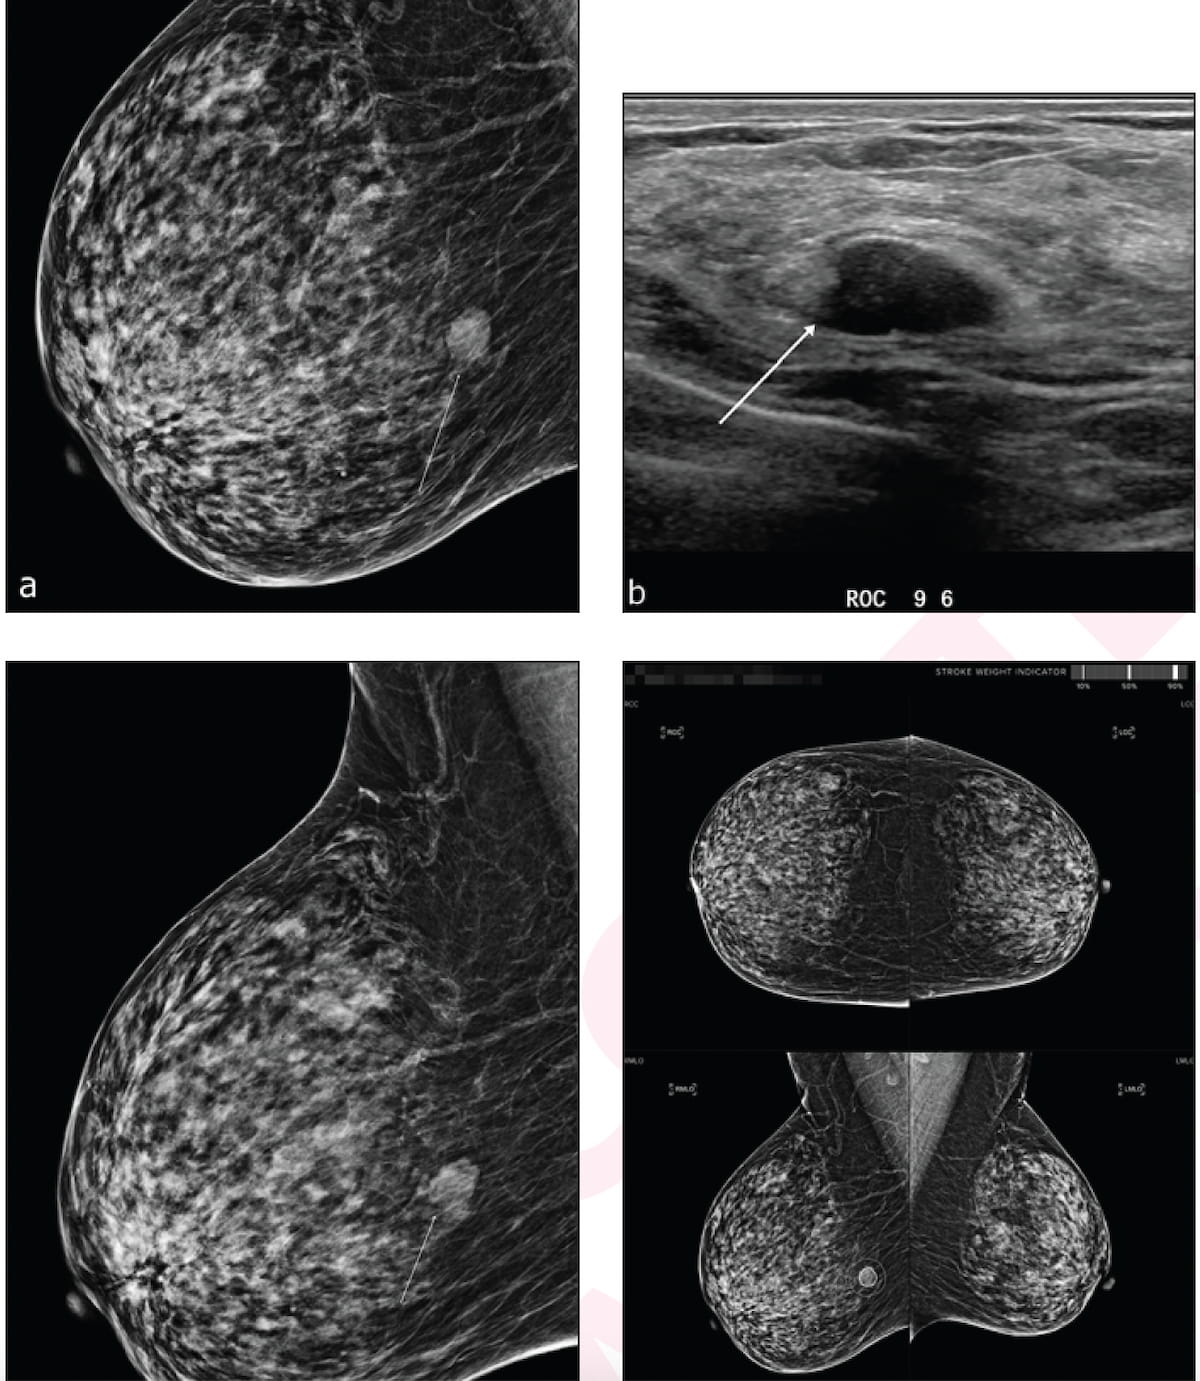

Adjunctive use of an artificial intelligence (AI) software demonstrated nearly equivalent sensitivity and over 28 percent higher accuracy in comparison to radiologist assessment of breast ultrasound images for breast lesions, according to new research presented at the recent Society of Breast Imaging (SBI) conference.

Emerging breast ultrasound research showed the use of computer-aided diagnosis (CAD), powered by deep learning, led to 24 percent and 36.9 percent improvements in accuracy and specificity, respectively, in the use of BI-RADS classifications by radiologists without breast ultrasound expertise.